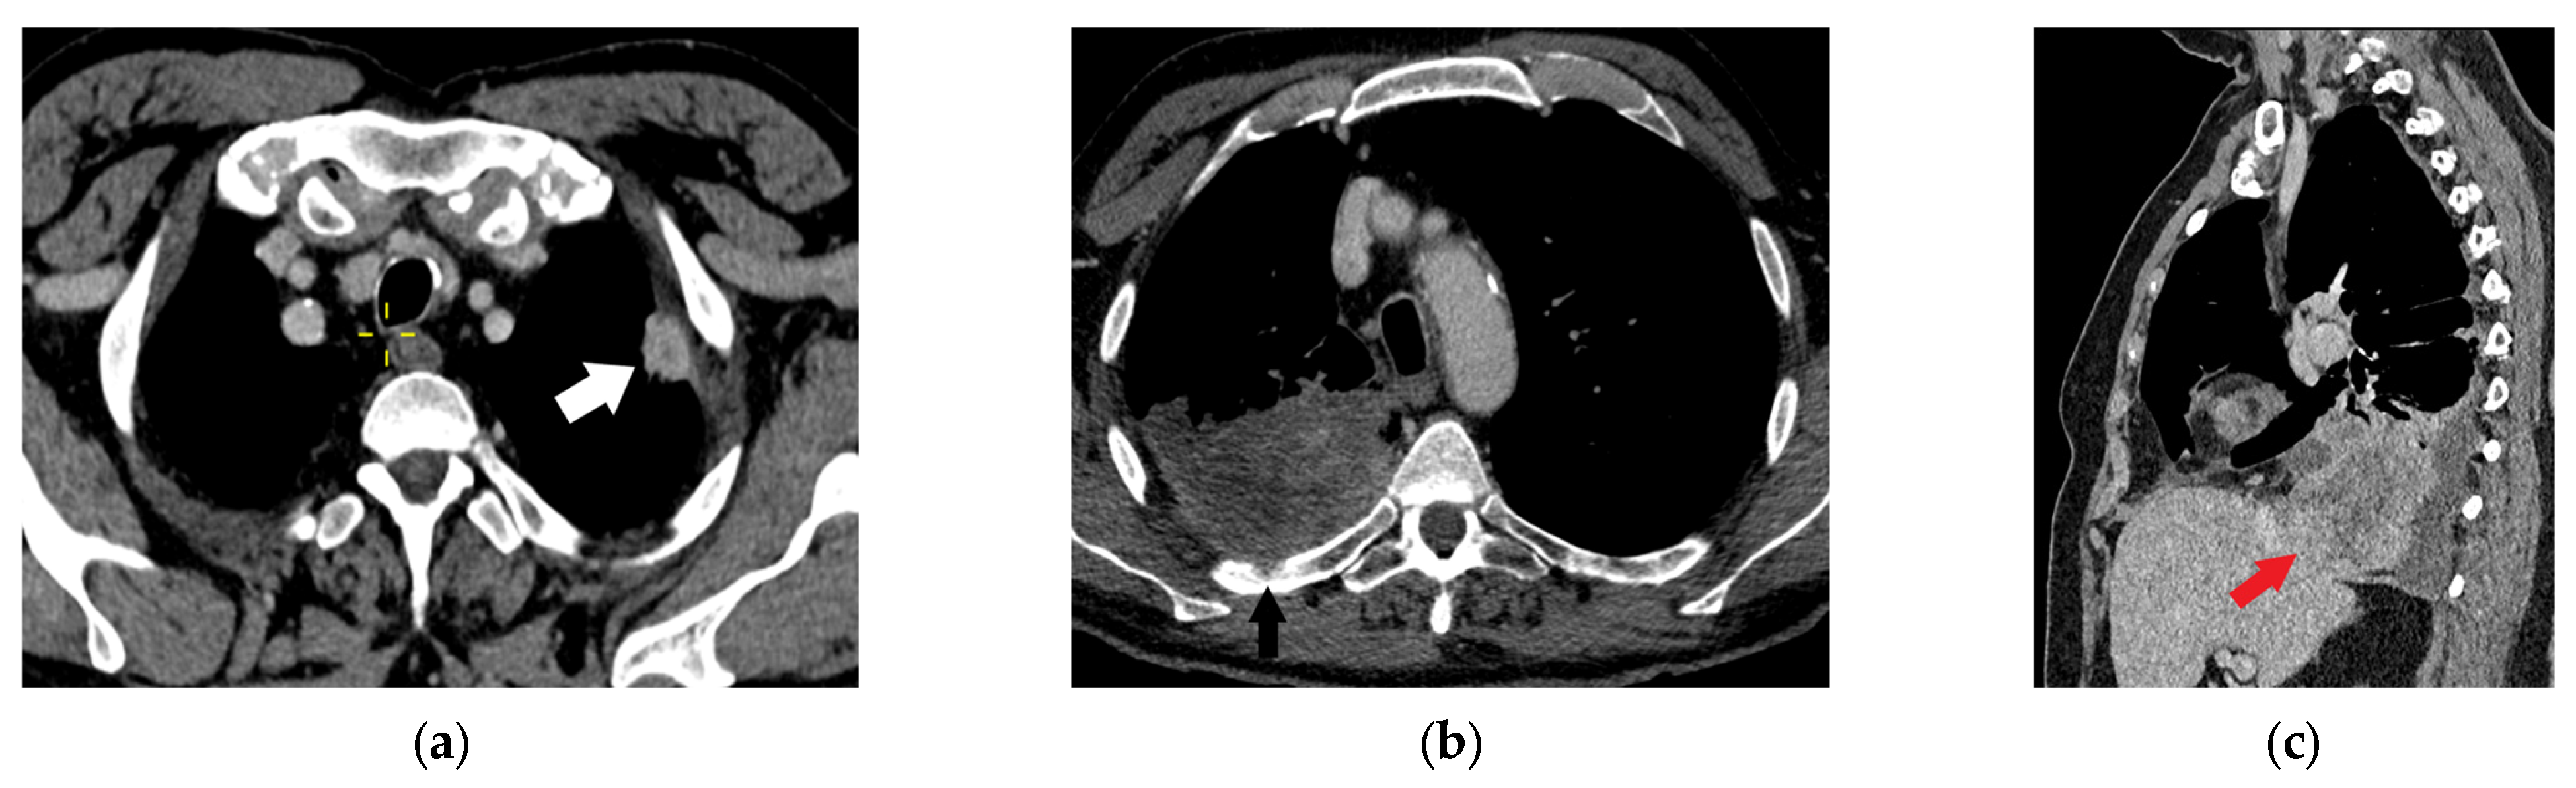

| T4 | Tumor > 7 cm in the greatest dimension Invasion of the mediastinum, thymus, trachea, carina, recurrent laryngeal nerve, vagus nerve, esophagus, or diaphragm Invasion of the heart, great vessels (aorta, superior or inferior vena cava, intrapericardial pulmonary arteries or veins), supra-aortic arteries, or brachiocephalic veins Invasion of subclavian vessels, vertebral body, lamina, spinal canal, cervical nerve roots, or brachial plexus Separate tumor nodule(s) in a different ipsilateral lobe than that of the primary | Signs of mediastinal invasion: infiltration of the mediastinal fat or structures that indicate the T4 stage, tumor–mediastinum contact length of more than 3 cm, an obtuse angle between the tumor and the mediastinum [37] Signs of vascular invasion: disappearance of the fat layer between the mass and the vessel, the angle between the mass and vessel wall >90°, a stenosis or deformation of the vascular lumen [41,42] |

3.4.2. T3 and T4 Categories